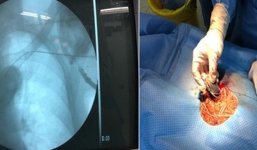

Cụ ông 101 tuổi đi qua cửa tử với chiếc máy tạo nhịp trong tim